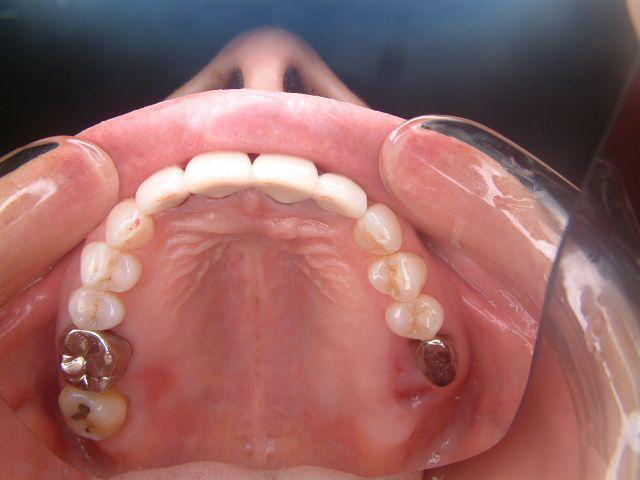

2112 連結MB

※上記の患者さんの近親者

綺麗になった歯をご覧になって

ご自分の歯も治す決意をされたそうです

個歯トレー&各個トレー&テック

患者さんは、自分のイメージした補綴物

が出来上がってくるか不安だと思いますが

テックで歯の長さや、形態を確認することで

信頼関係が出来上がるようです。 |